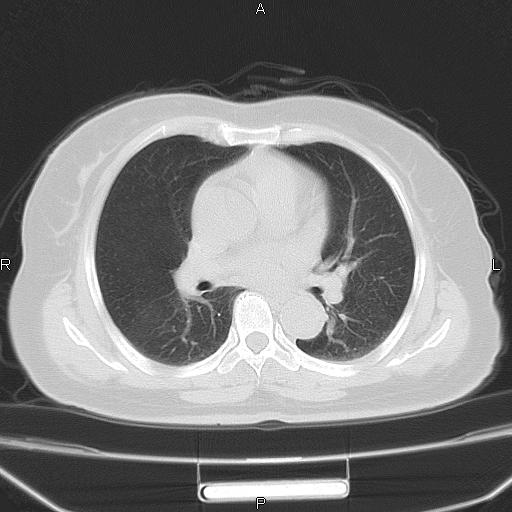

胸腺瘤

女、63Y 双眼睑下垂,早轻晚重。 胸腺瘤???

结果胸腺瘤